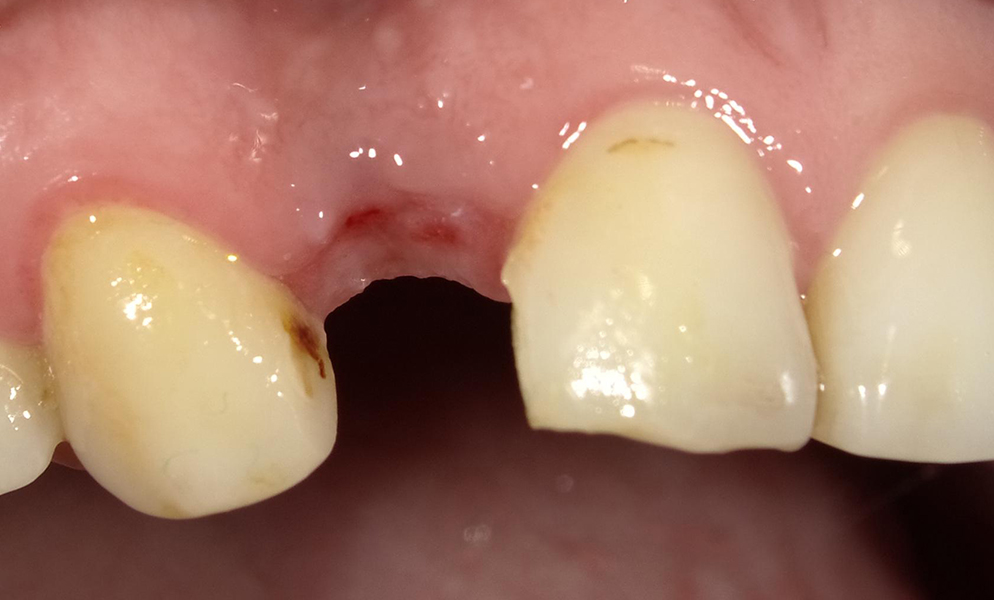

![]() |

| Single anterior tooth missing space restored with a narrow dental implant (Bicon, USA) | |